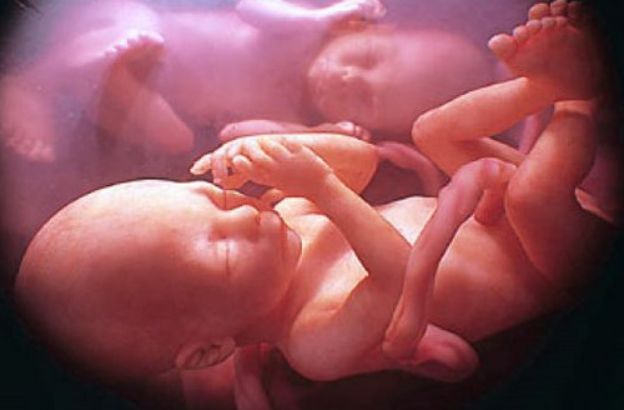

L’interazione sociale comincia nel feto: il caso dei gemelli ripresi con l’ultrasonografia

gemelli

I ricercatori hanno osservato i feti utilizzando un particolare tipo di tecnica medica chiamata ultrasonografia a quattro dimensioni, attraverso la quale è possibile ottenere immagini tridimensionali ricostruite in sequenza temporale.

Le analisi sulle coppie di gemelli sono avvenute alla quattordicesima e alla diciottesima settimana di gestazione e, in entrambi i periodi, i ricercatori hanno riscontrato nei fratelli, alcuni movimenti volontari e rivolti l'uno nei confronti dell'altro.

I gemelli, già a partire dalla quattordicesima settimane e con una decisa intensificazione durante la diciottesima, si cercano l’un l’altro con movimenti intenzionali e utilizzano il suddetto movimento quasi per coccolarsi.